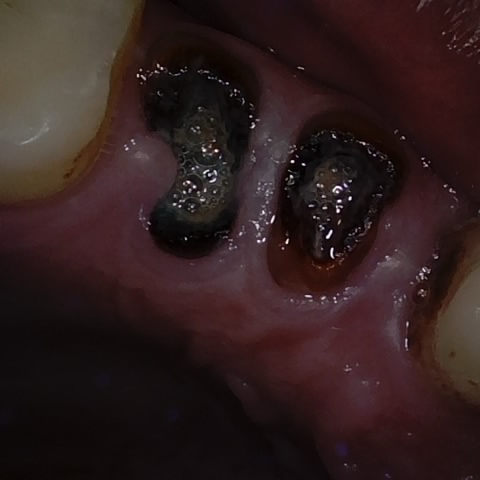

Annotated as "Good"